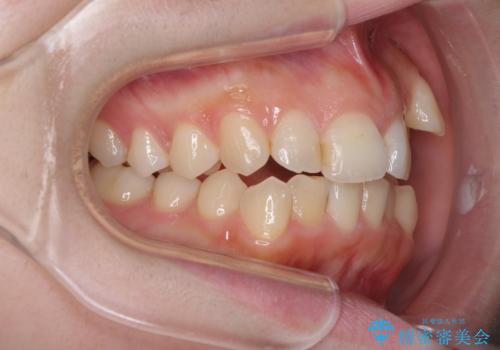

顕著な八重歯をインビザラインで治せるところまで改善

- 顕著な八重歯など、上下前歯のデコボコとスペースを気にして来院された患者様です。

八重歯改善には第一小臼歯の抜歯が必要であり、移動量が多いことから補助装置により八重歯を引き込むこととしました。

インビザラインでの治療をご希望であったので、インビザラインにて行うこととしましたが、右側前歯の改善にはワイヤー矯正が必要となる可能性があることをお伝えした上で治療を開始しました。

補助装置だけでなく、部分的にワイヤー矯正も使用しましたが、上下のスペースは改善しきれず、側切歯(前から2番目の歯)や顕著な八重歯は、インビザラインで治療するには限界があることがよく分かりました。

より良い仕上がりを希望される場合には、ワイヤー装置による矯正治療がお勧めとなります。